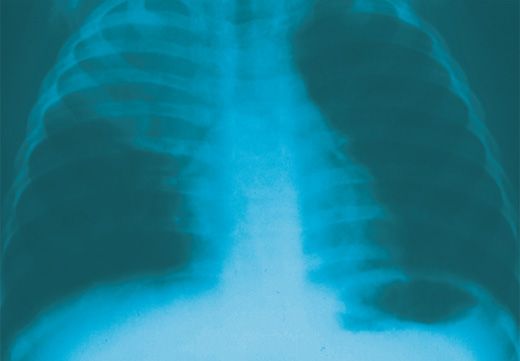

A 56-year-old man presented to the ED after 4 days of hemoptysis and intermittent left chest pain. He said he had been treated for "pneumonia" twice during the previous month. Chest films revealed bilateral infiltrates (arrows). Renal biopsy found pauci-immune necrotizing glomerulonephritis with cellular crescent formation, consistent with Wegener granulomatosis, a multiorgan disease that most frequently affects the respiratory system and kidneys.

Image courtesy of Shital Patel, MD and Dean Gianakos, MD.